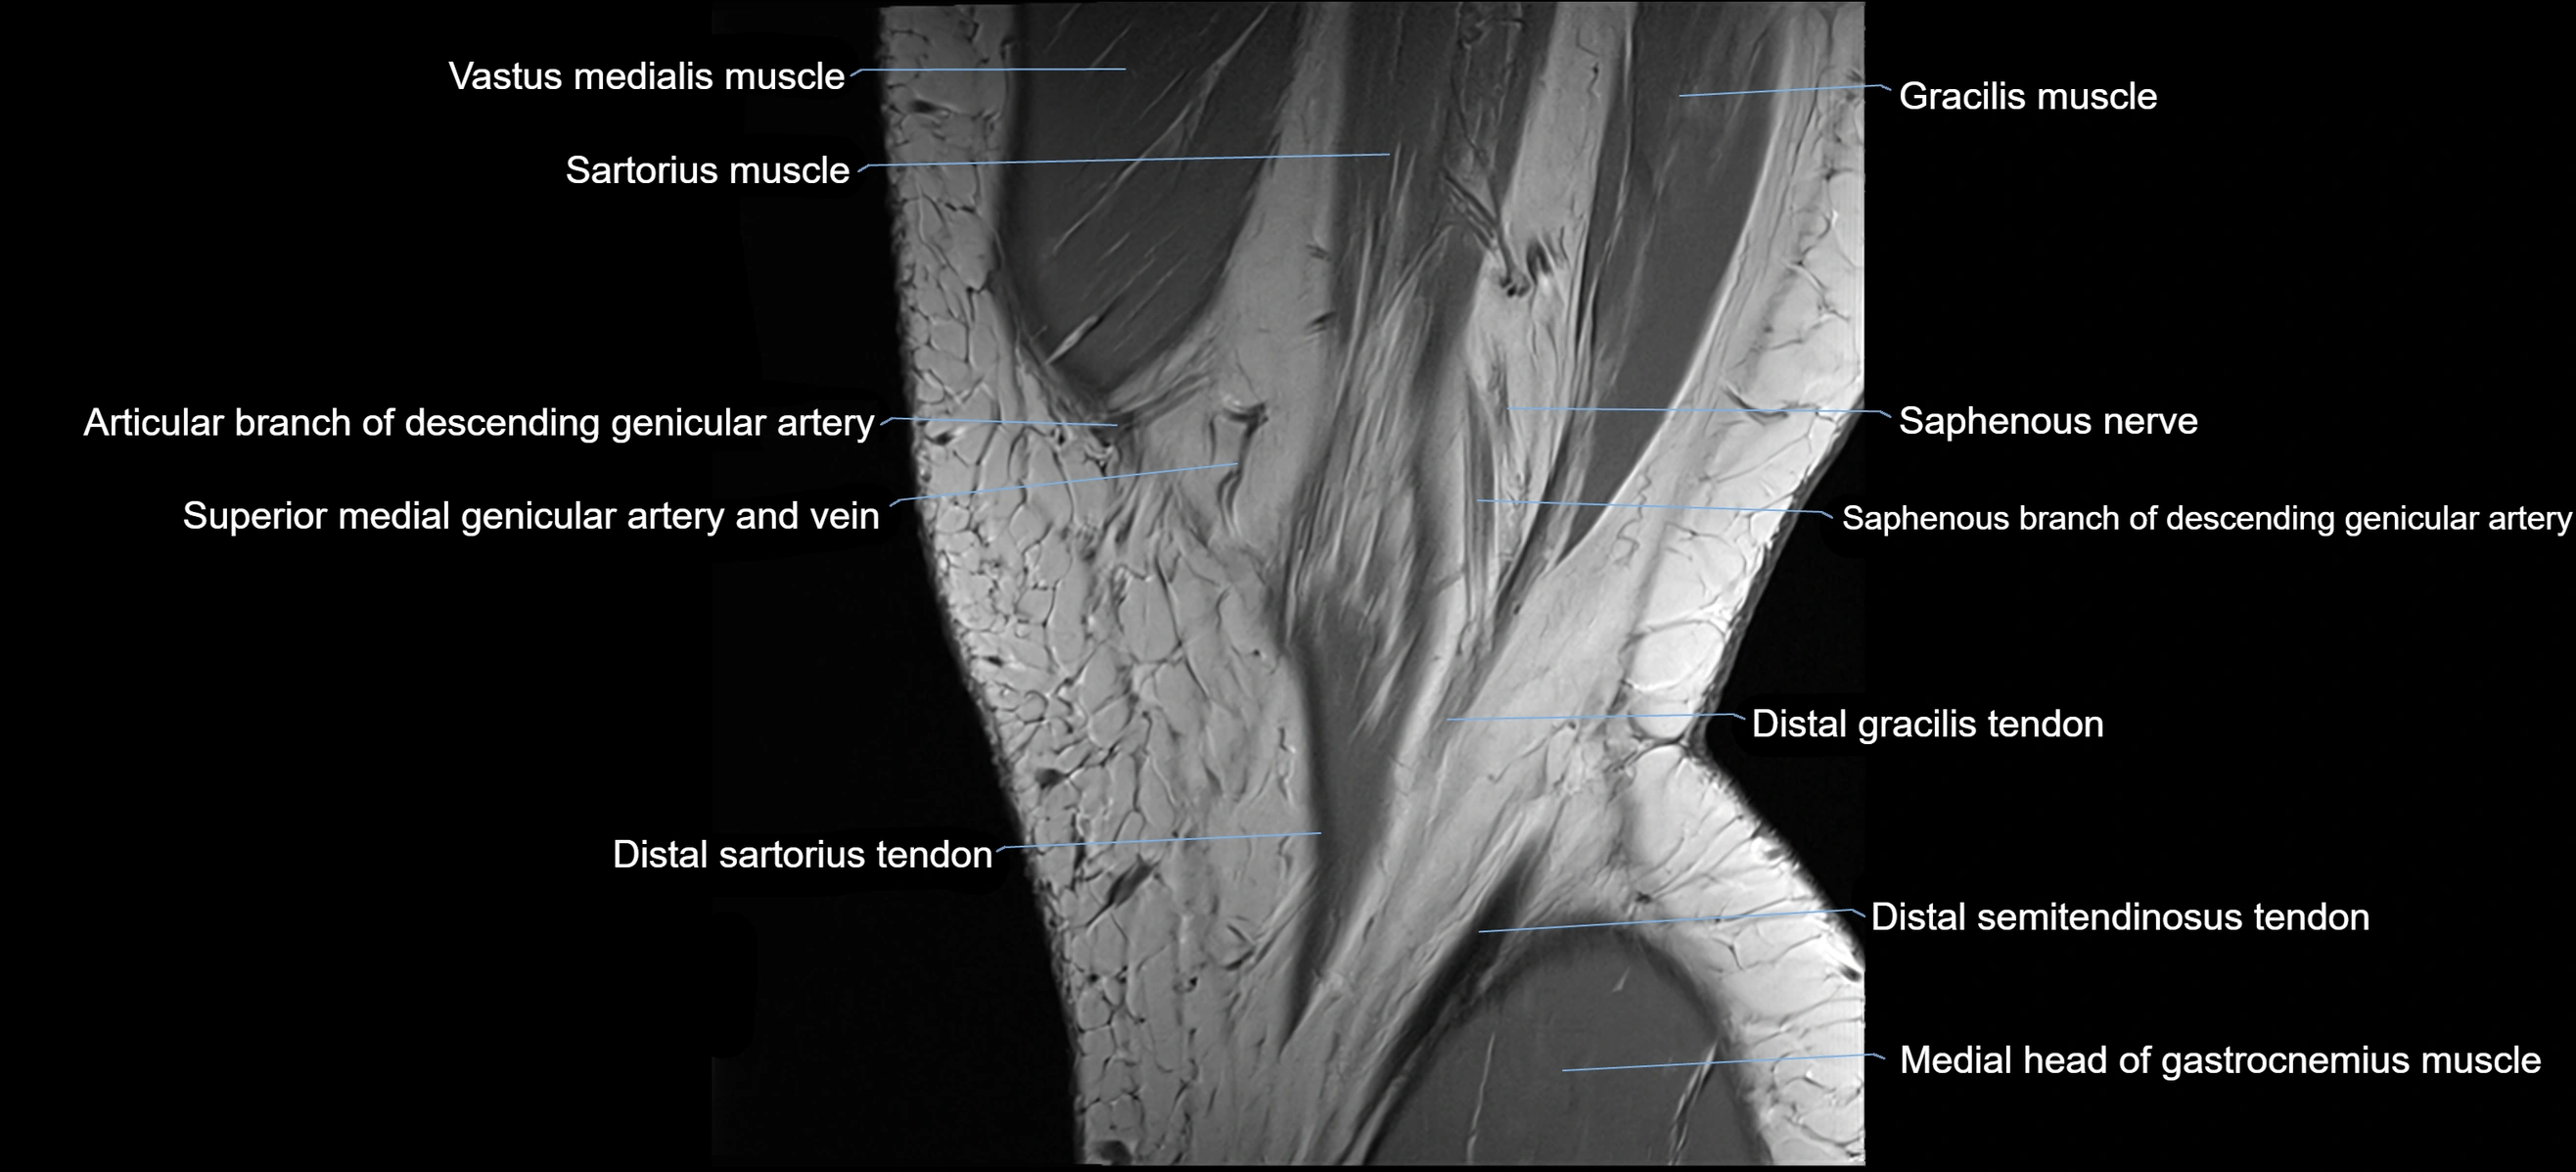

- Gracilis tendon (Distal)

- Medial head of gastrocnemius muscle

- Saphenous nerve

- Sartorius muscle

- Sartorius tendon (Distal)

- Semitendinosus muscle

- Descending genicular artery (Articular branches)

- Descending genicular artery (Saphenous branch)

- Superior medial genicular artery